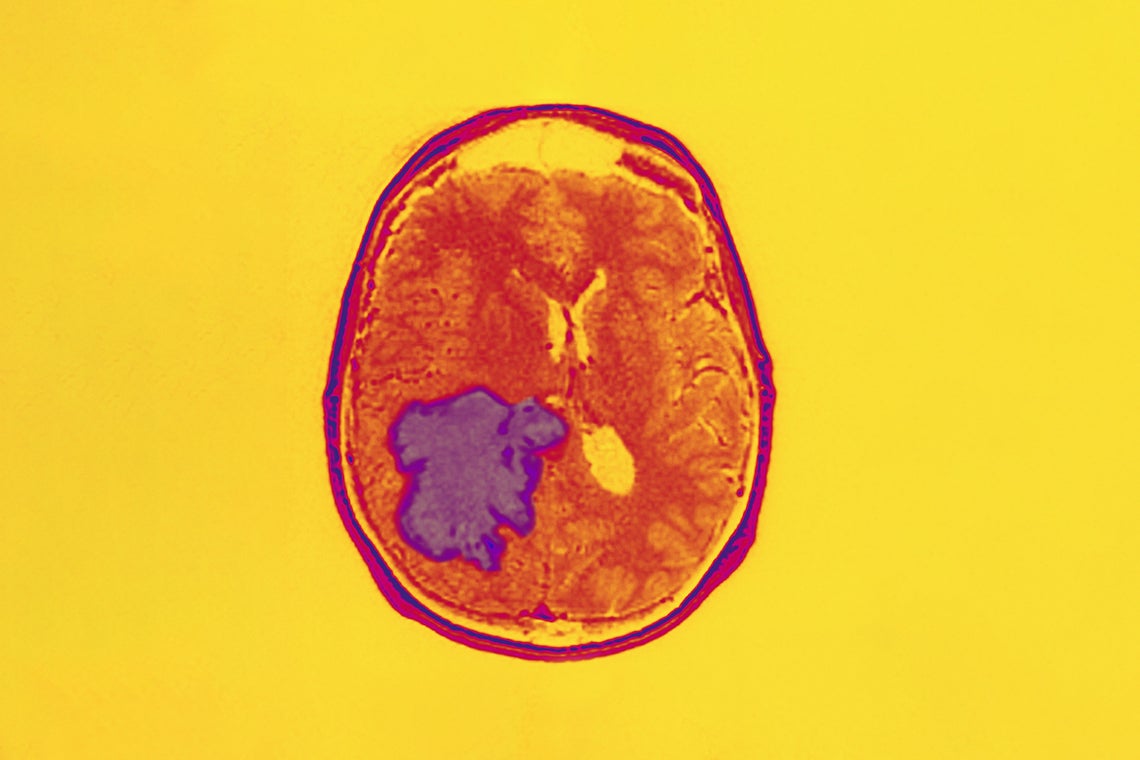

(Photo by BSIP/Universal Images Group/Getty Images)

Glioblastoma is the most common and aggressive form of brain cancer – the average life expectancy after a diagnosis is around 15 months.

For decades, scientists have searched for ways to treat GBM, including conventional surgery, radiation, chemotherapy and targeted therapy. GBM cells quickly reproduce and invade nearby brain tissue and are notoriously difficult to eradicate by conventional surgery. These cells also develop resistance to chemotherapy or targeted therapy. As a result, patients usually relapse after undergoing currently available treatment protocols.